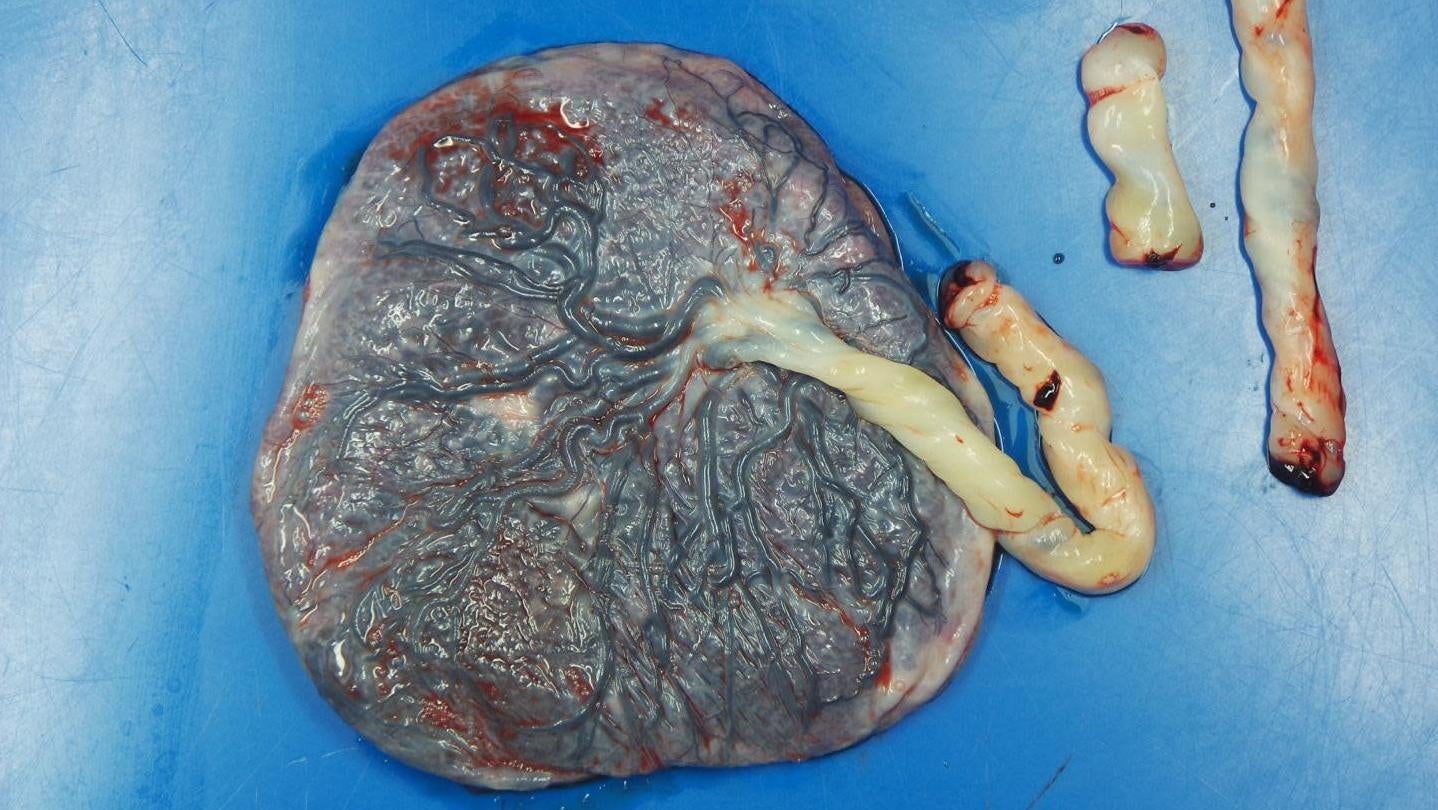

In this new study, published in the American Journal of Clinical Pathology, researchers examined the placentas of 16 pregnant women diagnosed with covid-19. They were then compared to (previously examined) placentas from women who gave birth prior to 2019.

One of the women suffered a miscarriage at week 16, while another had an early delivery at week 34. Among those who had a live birth, there were no reported health problems among the babies. But there was evidence of injury to the blood flow of the placenta in 12 of the 15 women—a rate of blood flow injury higher relative to the control group. Six women also had blood clots in their placenta and five had a smaller-than-expected placenta.

“They were healthy, full-term, beautifully normal babies, but our findings indicate a lot of the blood flow was blocked off and many of the placentas were smaller than they should have been,” said study author Emily Miller, an assistant professor of obstetrics and gynecology at Northwestern University in Chicago, in a statement released from the university. “Placentas get built with an enormous amount of redundancy. Even with only half of it working, babies are often completely fine. Still, while most babies will be fine, there’s a risk that some pregnancies could be compromised.”